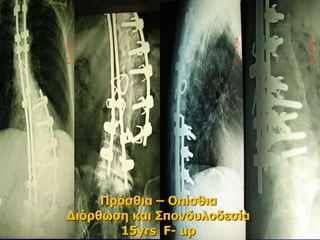

Πρόσθια – Οπίσθια

Διόρθωση και Σπονδυλοδεσία

15yrs F- up